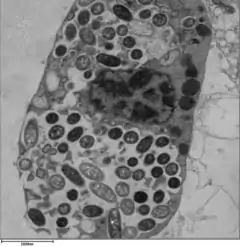

Legionella is a species that is known to infect and multiply within species of free-living amoeba. We know of at least 20 different species of free-living amoeba that support the intracellular replication of L. pneumophila. [10] This bacterium can infect and survive within the amoeba genera which includes: Acanthamoeba, Vermamoeba and Naegleria. L. pneumophila are surrounded by an amoeba-resistant cyst while residing inside the amoeba, allowing them to survive harsh environmental conditions such as chlorine, which is commonly used in water treatment systems.[11]

In humans, L. pneumophila invades and replicates inside macrophages. The internalization of the bacteria can be enhanced by the presence of antibody and complement, but is not absolutely required. Internalization of the bacteria appears to occur through phagocytosis. However, L. pneumophila is also capable of infecting non-phagocytic cells through an unknown mechanism. A rare form of phagocytosis known as coiling phagocytosis has been described for L. pneumophila, but this is not dependent on the Dot/Icm (intracellular multiplication/defect in organelle trafficking genes) bacterial secretion system and has been observed for other pathogens.[17] Once internalized, the bacteria surround themselves in a membrane-bound vacuole that does not fuse with lysosomes that would otherwise degrade the bacteria. In this protected compartment, the bacteria multiply.

Legionella-containing vacuole

For Legionella to survive within macrophages and protozoa, it must create a specialized compartment known as the Legionella-containing vacuole (LCV). Through the action of the Dot/Icm secretion system, the bacteria are able to prevent degradation by the normal endosomal trafficking pathway and instead replicate. Shortly after internalization, the bacteria specifically recruit endoplasmic reticulum-derived vesicles and mitochondria to the LCV while preventing the recruitment of endosomal markers such as Rab5a and Rab7a. Formation and maintenance of the vacuoles are crucial for pathogenesis; bacteria lacking the Dot/Icm secretion system are not pathogenic and cannot replicate within cells, while deletion of the Dot/Icm effector SdhA results in destabilization of the vacuolar membrane and no bacterial replication.[25][26]